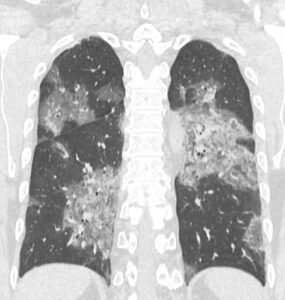

320列マルチスライスCT(MDCT)

コロナ肺炎